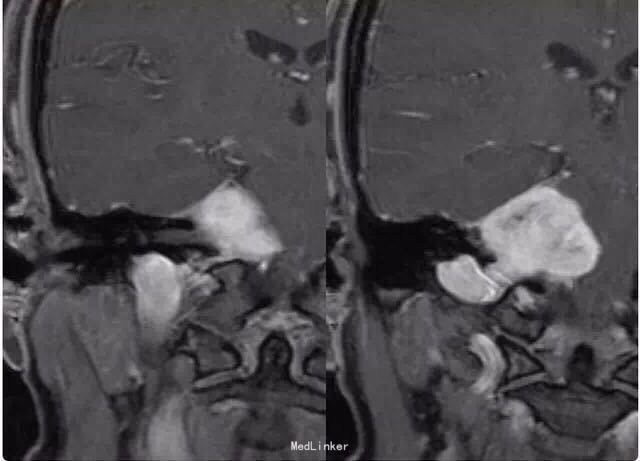

女性患者,34 岁,主因头痛、右耳听力损害以及平衡障碍 3 个月入院。

行头颅影像学检查、轴位 T1 像、轴位增强后 T1 像、冠状位增强后 T1 像以及轴位 T2 像:显示在右侧桥脑小脑角部位有一边界清楚病灶,T1 为低信号,T2 为高信号,并且伴有强化;病灶扩展至右侧颈静脉孔区,导致颈静脉孔增宽,脑干、第四脑室和小脑变形。右侧内耳道正常,病灶无颅外扩展。轴位 T2 加权 GRE 成像显示多发性病灶内出血:

诊断为颈静脉孔区神经鞘瘤。 手术切除辅助以立体定向放疗。